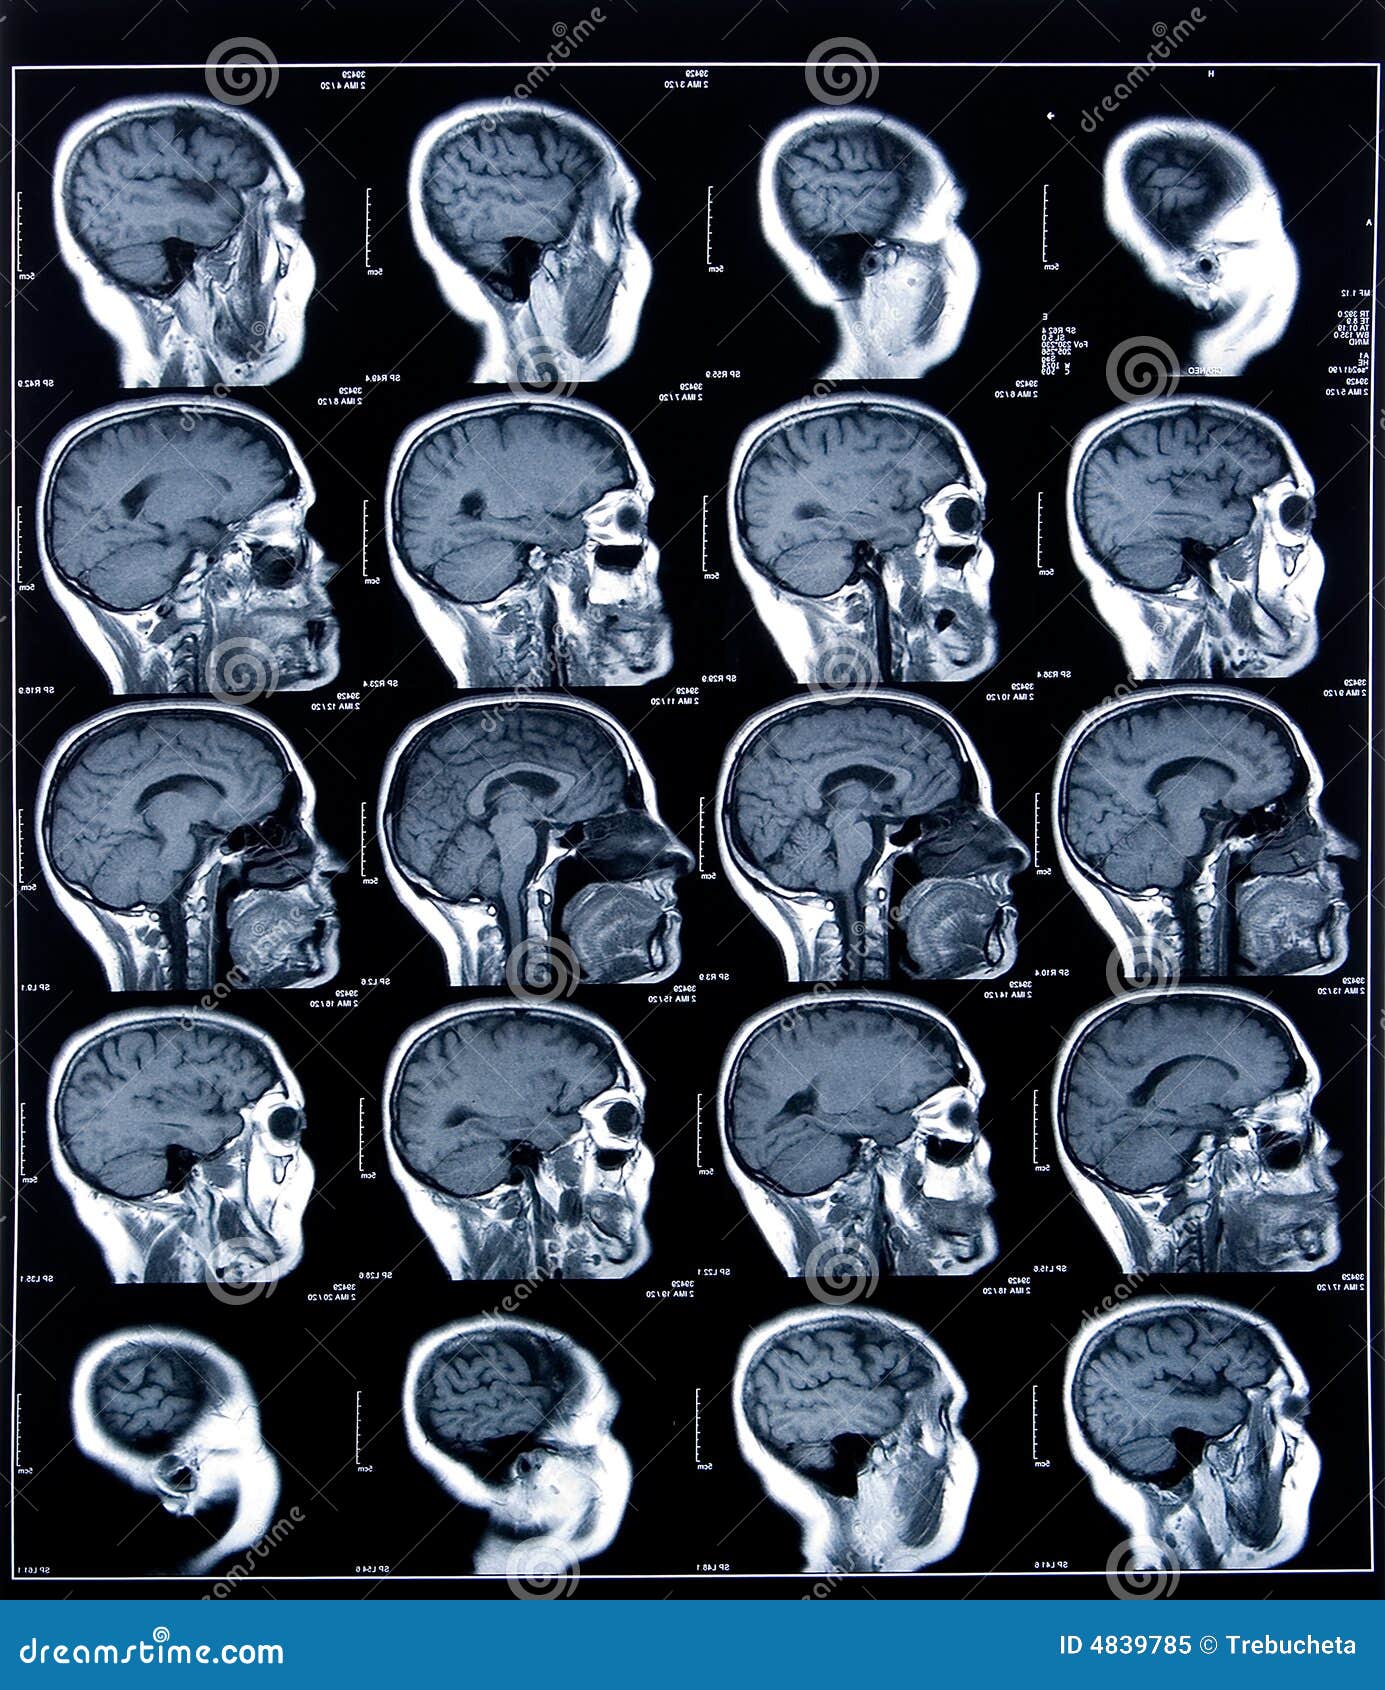

Шум в голове мрт головы

Шум в голове мрт головы 132 фотографий